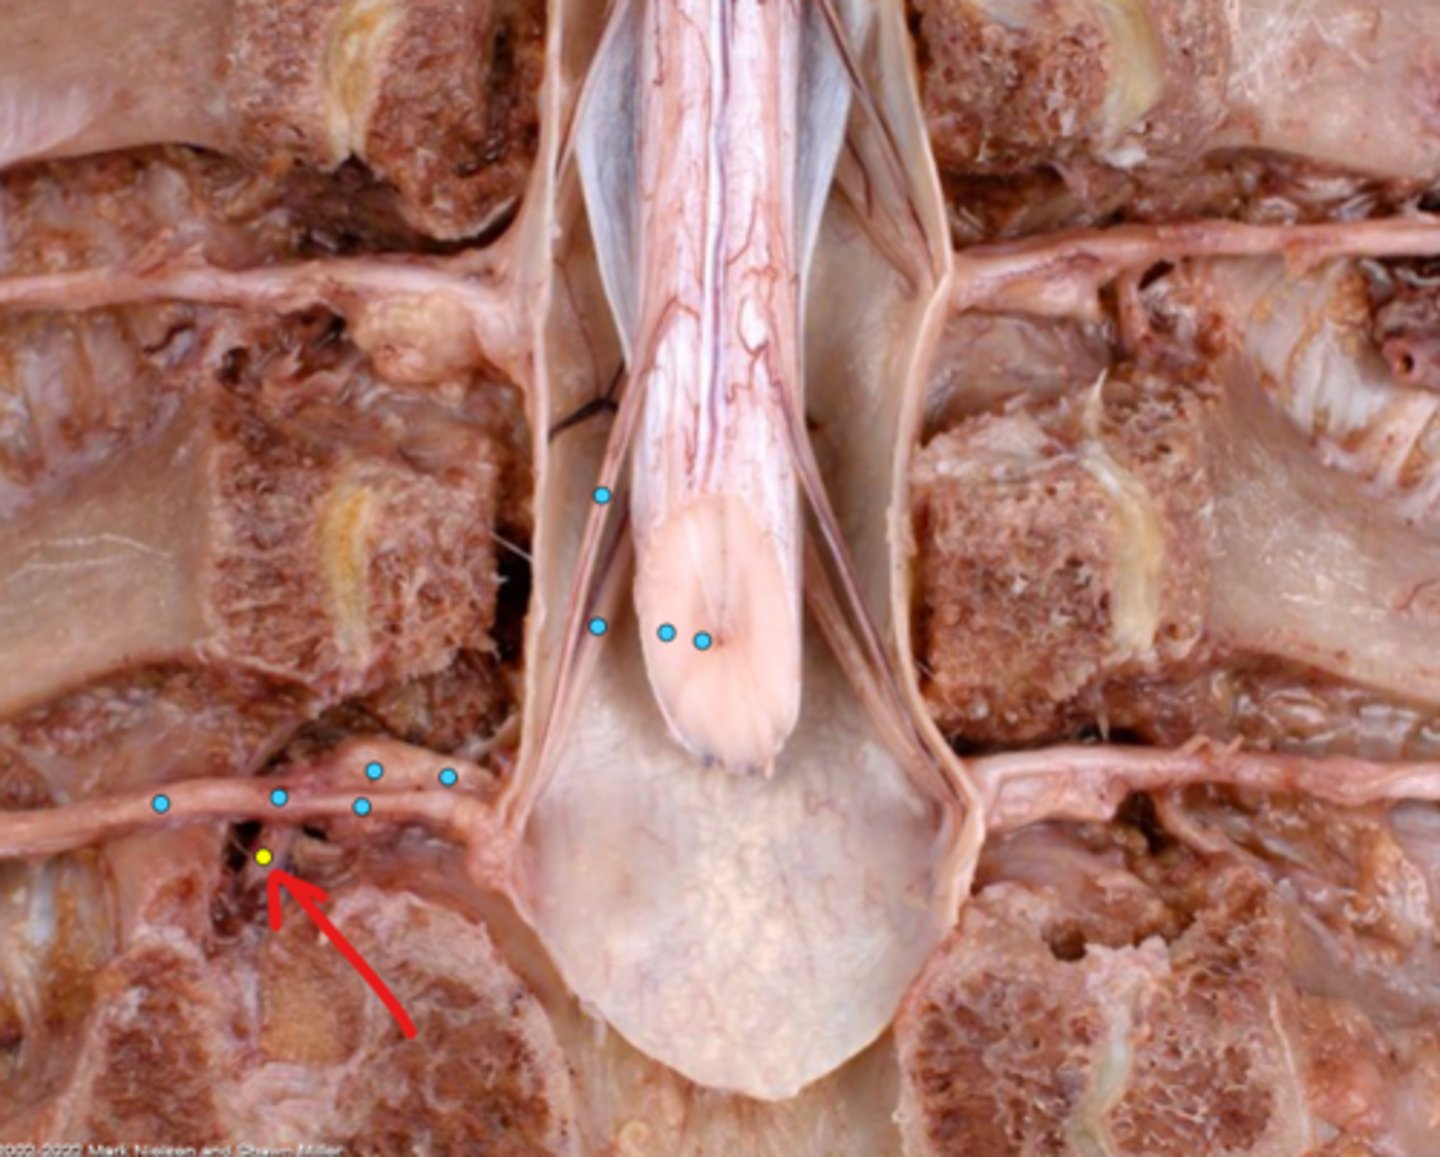

Intercostal nerve

Communicating ramus

Sympathetic trunk ganglion

Sympathetic trunk

Lesser splanchnic nerves

Greater splanchnic nerve

Anterior (ventral) ramus

Spinal nerve trunk

Posterior (dorsal) ramus

Spinal ganglion

Anterior (ventral) root

Posterior (dorsal) root

Anterior (ventral) rootlets

Posterior (dorsal) rootlets

White matter

Gray matter

Posterior (dorsal) rootlets

Anterior (ventral) rootlets

Spinal cord